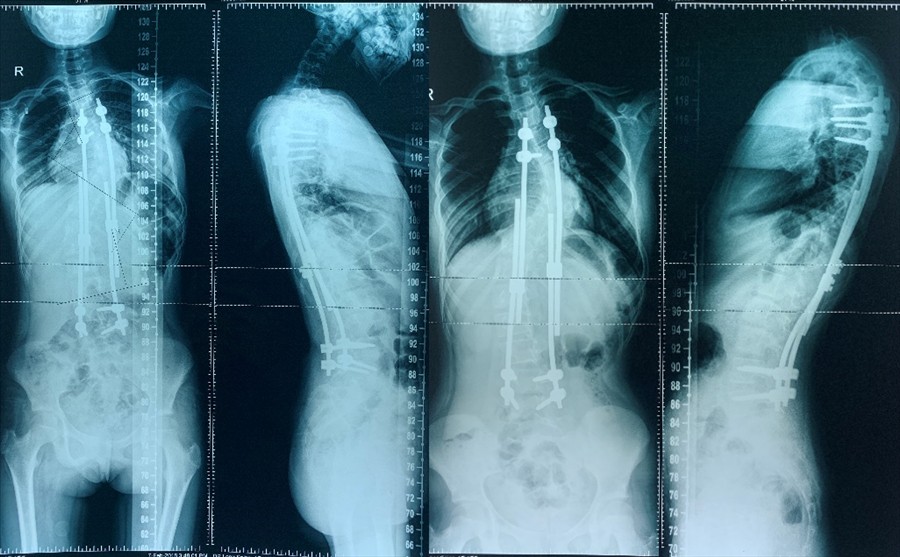

2018年01月生长棒及多米诺滑块置入术2018年03月术后复查

2018年08月第1次生长棒延长术2019年03月复查